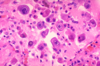

Obligate extracellular fungus that has silver stained cysts in tissues. Can cause interstitial pneumonia in AIDS patients. Causes death of type I pneumocytes and subsequent overproliferation of type II pneumocytes.

flying saucer appearing morphology. what kind of pneumonia do we expect to see with this agent?

Pneumocystis Jirovecii

PCP infection

pneumocystis jirovecii